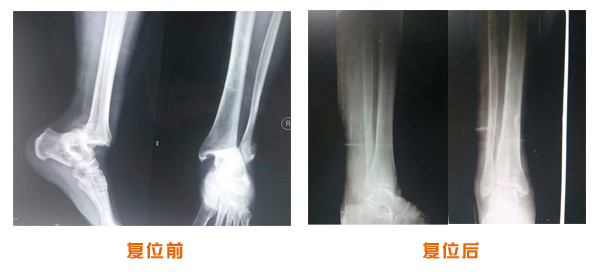

肥城市安駕莊梁氏骨科醫院是一所以梁氏手法正骨配合膏藥為特色的現代化專科醫院。

梁氏骨科術始創于清雍正年間,歷經八代,至今已有三百年歷史。據1929年泰安縣志載“梁瑞圖先生,字增生,號蓮峰,安駕莊人,精岐黃并發明接骨,凡跌打車凡跌打車軋皮不破而碎骨者......【詳細】 |